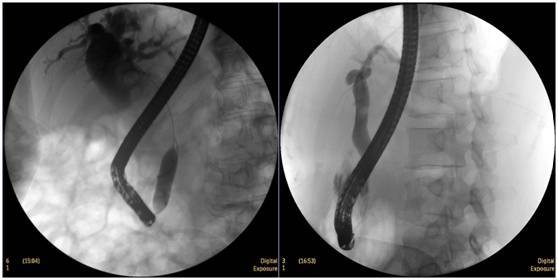

食管惡性腫瘤

食管癌并狹窄內(nèi)鏡下擴(kuò)張支架植入術(shù),支架在脊柱背景下依然能清晰顯示。